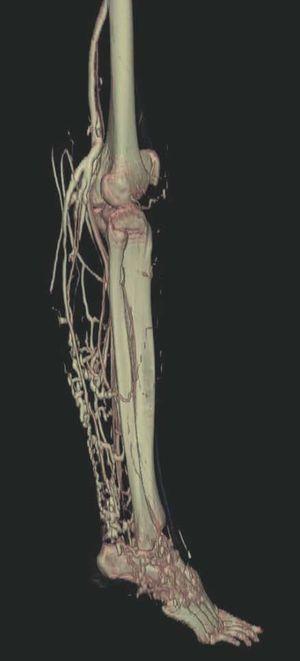

Hoy en día la utilización de los nuevos equipos TC multicorona y RM permiten la adquisición de imágenes con gran rapidez, pudiendo realizar reconstrucciones multiplanares de gran calidad, así como estudios angiográficos no invasivos13,23. Recientemente hemos estudiado 16 pacientes con síndrome de Klippel-Trenaunay mediante una venografía tomografía computarizada multicorte (TCM) o una venografía resonancia magnética tridimensional (RM-3D), utilizando imágenes axiales convencionales, reconstrucciones multiplanares (RMP), proyecciones de máxima intensidad (PMI) e imágenes tridimensionales (figs. 1-3). Las imágenes axiales convencionales fueron de utilidad para evaluar el tejido blando y el hueso y permitieron localizar el sistema venoso profundo y los vasos anómalos superficiales, determinando su relación con estructuras adyacentes. Las imágenes axiales, RMP y PMI fueron empleadas para trazar el origen, trayecto y extensión de las malformaciones venosas. Las imágenes de la superficie cutánea permitieron evaluar la localización y la extensión de la mancha en vino de Oporto y demostrar la hipertrofia de la extremidad. Las reconstrucciones tridimensionales permitieron demostrar las varicosidades y el origen y trayectoria de los vasos aberrantes (figs. 4 y 5). Ninguno de los pacientes requirió otra técnica complementaria invasiva (flebografía convencional) para confirmar el diagnóstico y planificar las estrategia terapéutica24.

Figura 4. Agenesia de la vena poplítea en paciente con síndrome de Klippel-Trenaunay.

Figura 5. Hipertrofia músculo-esquelética e hipoplasia de vena femoral superficial en paciente con síndrome de Klippel-Trenaunay.

Así, podemos concluir que una venografía TC o una venografía RM en 3D en niños y embarazadas para limitar la radiación puede ser la prueba de elección para estudiar a fondo una malformación vascular extensa localizada en una extremidad. Esta técnica permite conocer la localización exacta de la lesión en un plano tridimensional, detectando una posible infiltración musculoesquelética y extensión torácica y/o abdominopélvica, además permite valorar cambios en la densidad ósea (osteoporosis) y dismetrías, así como comprobar la existencia de sistema venoso profundo y su permeabilidad (figs. 6-9). También son de utilidad para detectar anormalidades del sistema venoso superficial, demostrar las presencia de venas aberrantes o ciáticas y determinar su extensión y vía de drenaje. Aunque estos procedimientos siguen siendo inferiores a la arteriografía o flebografía convencionales al no proporcionar el mismo grado de información sobre la hemodinámica de la malformación, representan un avance muy significativo, y en nuestra experiencia sólo será necesaria la complementación con procedimientos invasivos en casos de hipoplasias vasculares donde no esté claro el funcionamiento hemodinámico del vaso24,25.

Figura 7. La angio-tomografía axial computarizada (TAC) muestra tridimensionalmente la relación de los vasos con el tejido muscular.

Figura 8. Tras sustracción de tejidos blandos en la angio-tomografía axial computarizada (TAC) destacan venas anómalas en región gemelar y tobillo sobre plano óseo (vista lateral).

Figura 9. Detalle de la figura anterior (vista posterior).